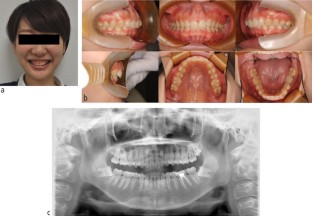

For orthodontic treatment, 0.018-inch standard edgewise brackets were bonded on the maxillary teeth. Two self-drilling TADs (diameter, 1.6 mm; length, 8 mm; Dual Top Auto Screw; Jeil Medical Corp, South Korea) were inserted into the buccal alveolar bone between the maxillary lateral incisors and canines to intrude the maxillary anterior teeth using an elastic chain. Before completion of opening the bite, positive crown torque of the upper incisors was achieved by torque moment generated with intruded force (Fig. 2A). After opening the bite, brackets were bonded on the mandibular teeth to create space between mandibular right central incisor and canine. However, after 12 months of intrusion, the crown of the maxillary right central incisor showed grey discoloration and a negative response to electric pulp tests (Fig. 2B). Furthermore, the patient reported severe spontaneous pain only in this tooth two days before visiting our clinic. However, no significant radiographic change was observed around the root apex of the maxillary right central incisor. Notably, moderate apical root resorption was observed in the maxillary right lateral incisor by the dental x-ray (Fig. 2C). From these symptoms, we thought traumatic pulp injury occurred on the right central incisor. Therefore, we removed the orthodontic force on the maxillary incisors with passive wire ligations between TADs and the upper canines, and 60 mg of loxoprofen sodium was administered three times a day for seven days. No more intrusion force to the upper incisors was applied because opening the bite had been completed. Six months after stopping orthodontic treatment, resolution of the crown discoloration was observed and the response to electric pulp testing was restored (Fig. 3A). Periapical radiography revealed a distinct radiolucency at the root apex (Fig. 3B). Two years after initiation of orthodontic treatment, the patient's gummy smile and overbite were corrected with a good intercuspal relationship. The missing mandibular right lateral incisor was replaced by direct bonding (Fig. 4A, Fig. 4B). Follow-up at four years after beginning of retention revealed stable smile aesthetics and tooth positions (Fig. 4C, Fig. 4D). Periapical radiographs showed marked root canal obliteration in the maxillary right central incisor and remodelling of the root apex in the maxillary right lateral incisor (Fig. 4E). The wire sequence used in this case is shown in Table 1.

(A) Post-treatment smiling facial photograph. (B) Post-treatment intra-oral photographs. (C) Smiling facial photograph four years after retention. (D) Intra-oral photographs four years after retention. (E) Dental x-ray at four years after retention. Marked root canal obliteration in the maxillary right central incisor and remodelling of the root apex in the maxillary right lateral incisor were shown